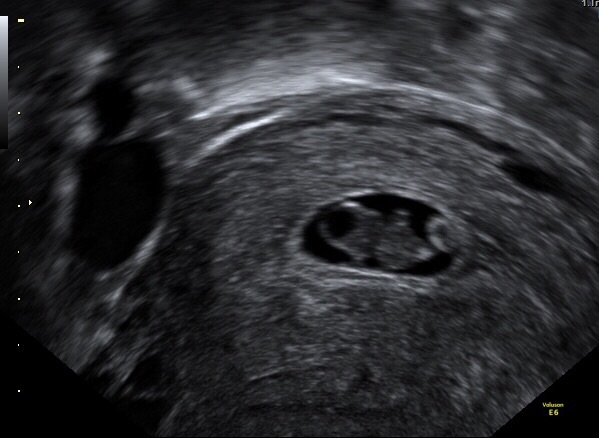

• Had our second ultrasound today, 9w1d. Heart rate was up to 166 this time, we even got to see the baby wiggle around. It's absolutely nuts to see the difference two weeks can make, we could actually make out arms, legs and head this time!